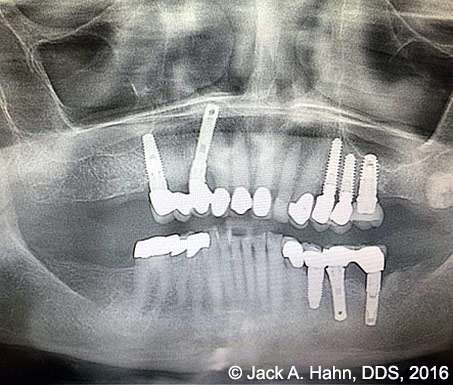

CASE #4 Trauma Case – Central Incisors Internal / External Resorption

Implants, that replace failed endo- or perio-compromised teeth, have a MUCH higher success rate with laser decontamination of the osteotomy site. LightScalpel laser surgical and perio laser tips ensure excellent access to extraction socket for the optimum removal of granulation tissue and socket decontamination (protocol involves manual curettage of the socket with alternating rinsing and lasing).

The patient, a 17-year-old female was involved in a water slide accident 3 years ago. As a result, both central incisors were avulsed and an endodontist replanted them. Both teeth exhibited internal and external resorption. Dr. Hahn extracted both central incisors, removed all the root fragments and sanitized the sites with the LightScalpel laser which also eliminated any granulation tissue. The #8 area was prepared to place a Hahn 4.3×13 Implant and #9 was prepared for a Hahn 3.5×13. 3mm tall Hahn healing abuts were placed slightly below the gingival-tissue level to help develop an emergence profile when at the restoration time in 4 months. Upon seeing the x-ray, Dr. Hahn tightened the healing abutment on #9 to be sure that it was completely seated on the implant. 45nucm. stability was achieved on both implants. He then placed some bone putty to seal any openings. To be on the safe side, he decided to place a temporary partial instead of immediate temporary prosthetics.